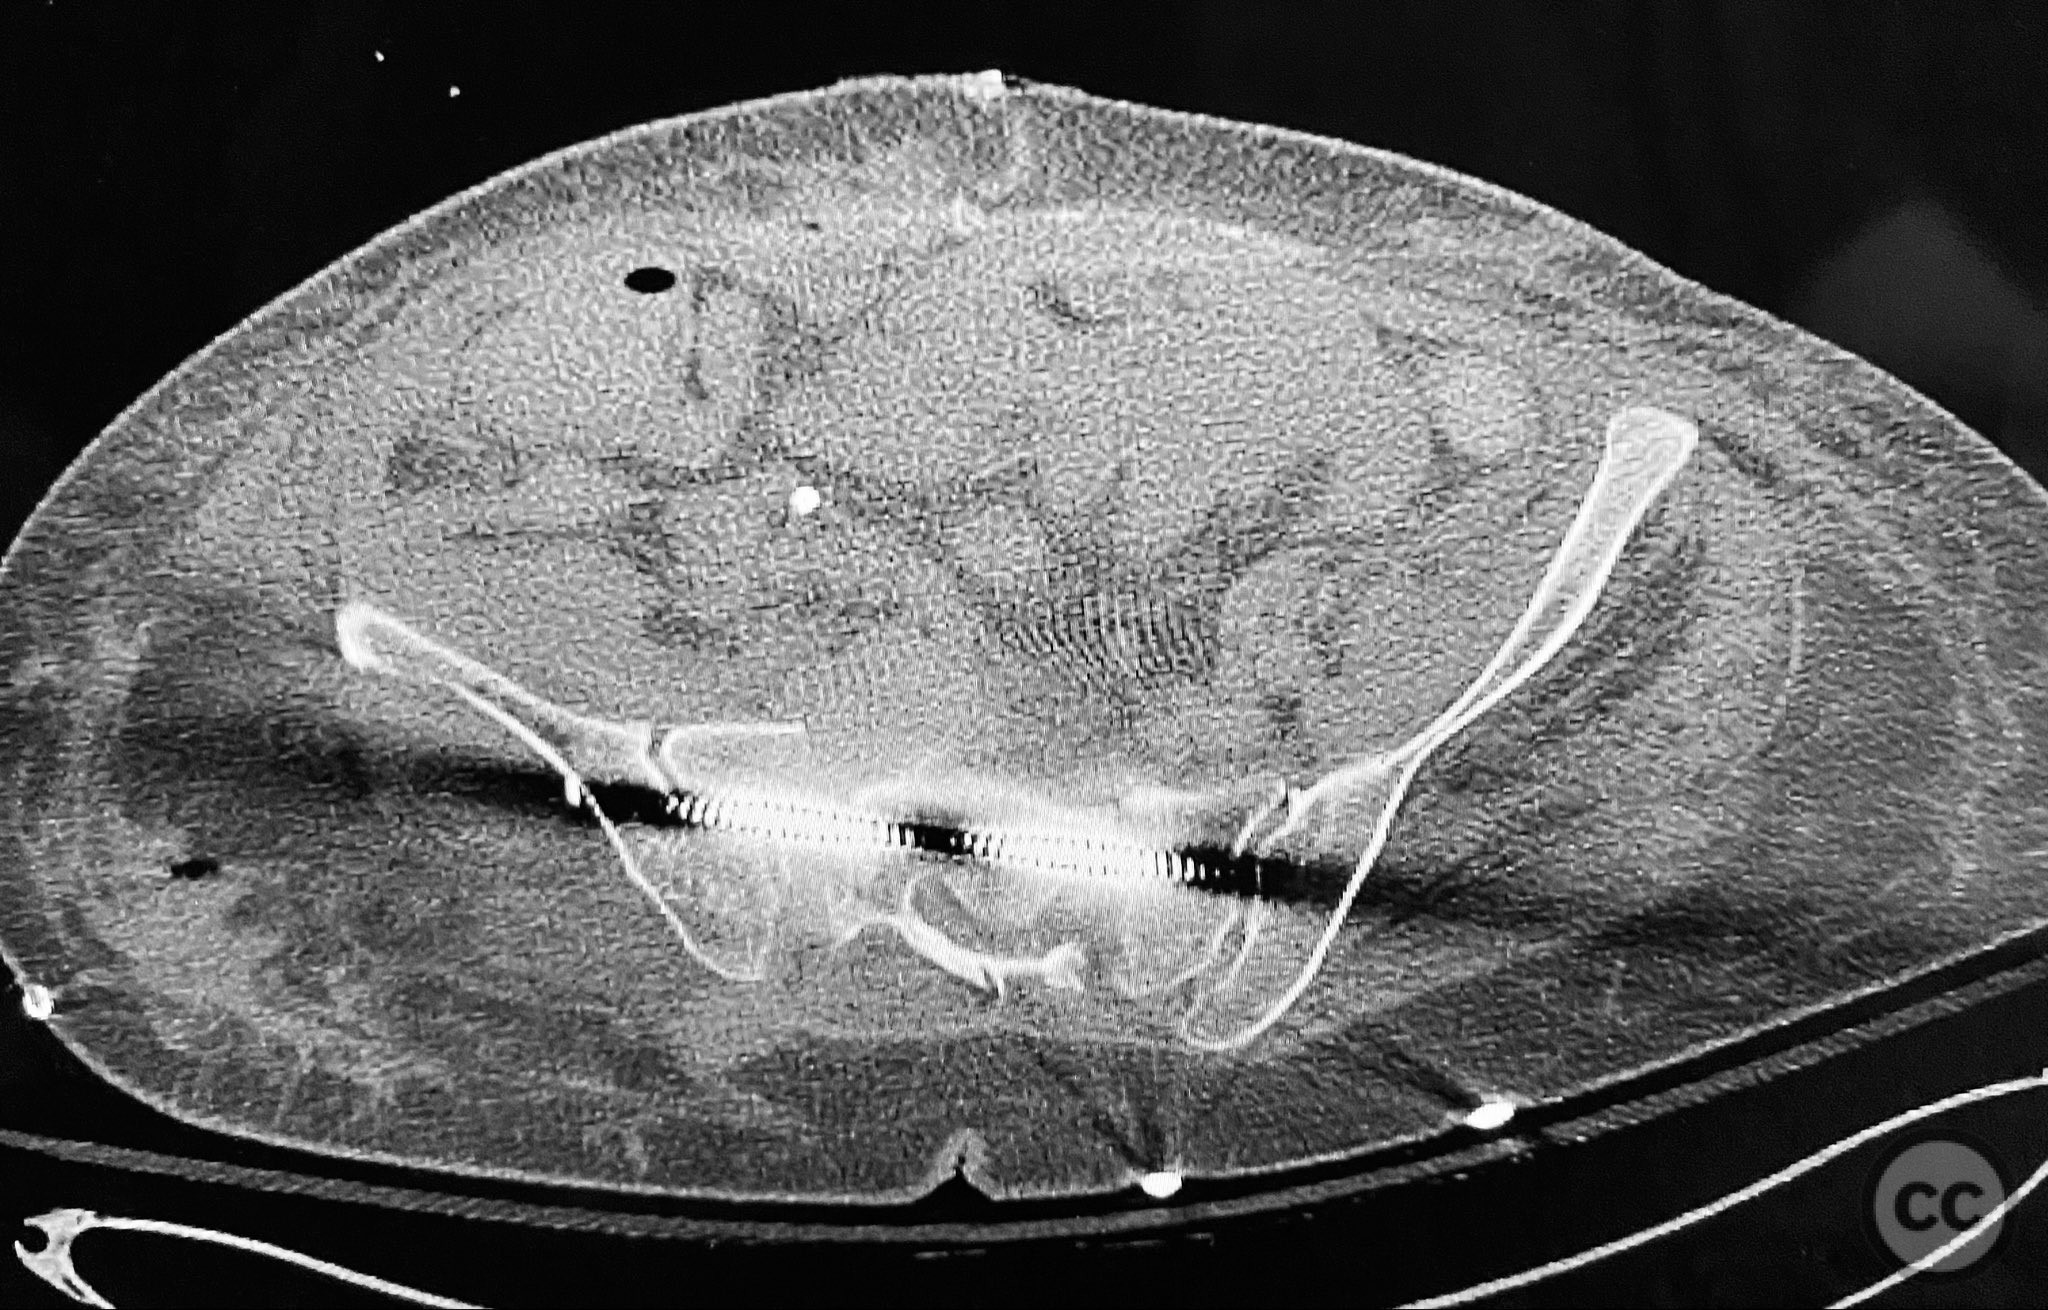

Clinical and radiological findings:  An elderly patient sustained multiple traumatic injuries, including complex unstable pelvic ring disruption (AO/OTA 61-C, likely C1 or C2 based on instability and comminution), comminuted proximal femoral fracture (AO/OTA 31-A3 or 31-B, depending on trochanteric or neck involvement), and significant abdominal trauma necessitating intra-abdominal packing. Initial clinical evaluation revealed hemodynamic instability and poor bone quality consistent with advanced age. Distal femoral traction was applied for provisional reduction. Radiological assessment was limited by osteopenia, fracture comminution, and the presence of abdominal packing materials.

Anatomical surgical approach:  Percutaneous iliosacral screw fixation was performed through small lateral gluteal incisions, with blunt dissection to the outer table of the os ilium. Under fluoroscopic guidance, guidewires were advanced across the sacroiliac joint into the S1 body, followed by cannulated screw insertion. For the proximal femur, a longitudinal incision was made proximal to the greater trochanter, splitting the fascia lata and gluteus medius fibers to access the piriformis fossa. A guidewire was inserted into the medullary canal, followed by sequential reaming and insertion of an intramedullary nail.

Intraoperative imaging was challenging due to osteopenic bone, fracture comminution, and interference from abdominal packing. Accurate identification of safe osseous corridors for iliosacral screw placement required multiple fluoroscopic projections and careful attention to pelvic landmarks. Bone quality necessitated cautious screw advancement to avoid iatrogenic cortical breach. After pelvic fixation, intramedullary nailing of the proximal femur proceeded without complication. Abdominal packing was removed and laparotomy wound closed after skeletal stabilization. Early mechanical stabilization of both pelvic and femoral injuries was prioritized to optimize survivability in this multiply injured elderly patient.